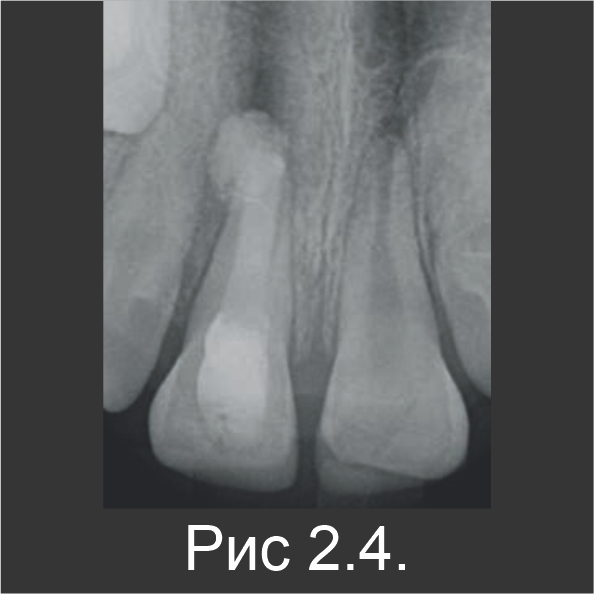

Резец остался в несформированном состоянии (с открытым апексом), остановившись в развитии по причине некроза пульпы. В течение первого посещения резец вскрыли, после чего корневой канал промыли гипохлоритом натрия, чтобы удалить некротические ткани. Затем канал просушили и заполнили пастообразной гидроокисью кальция на 2 недели (рис. 2.3). В течение второго посещения, после удаления гидроксида кальция канал заполнили Biodentine™ (рис. 2.4).

На рентгенограмме видна перфорация Biodentine™ в зоне апекса.